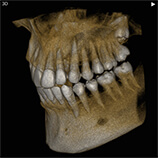

当クリニックでは歯科用CT装置を導入しています。

歯科用の3次元CTにより、いままで以上に詳細な診断ができるようになりました。

インプラント、歯周病、根管治療(歯の根の治療)、顎関節症などの治療時に有効です。

※CT画像一例